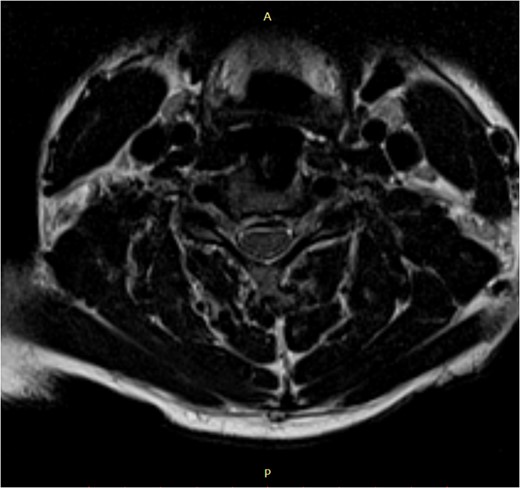

The patient's symptoms ceased in the early postoperative period. The neurological examination results were normal within a month (Nurick Grade: 0; Chile's mJOA: 16 points; recovery rate (RR) 91.6%). Patient was followed-up for 5 years.

MRI is the study of choice. Some researchers advocate the use of a low focal T1 and/or high T2 signal as a negative prognostic factor regarding post-treatment outcome, while others defy it.